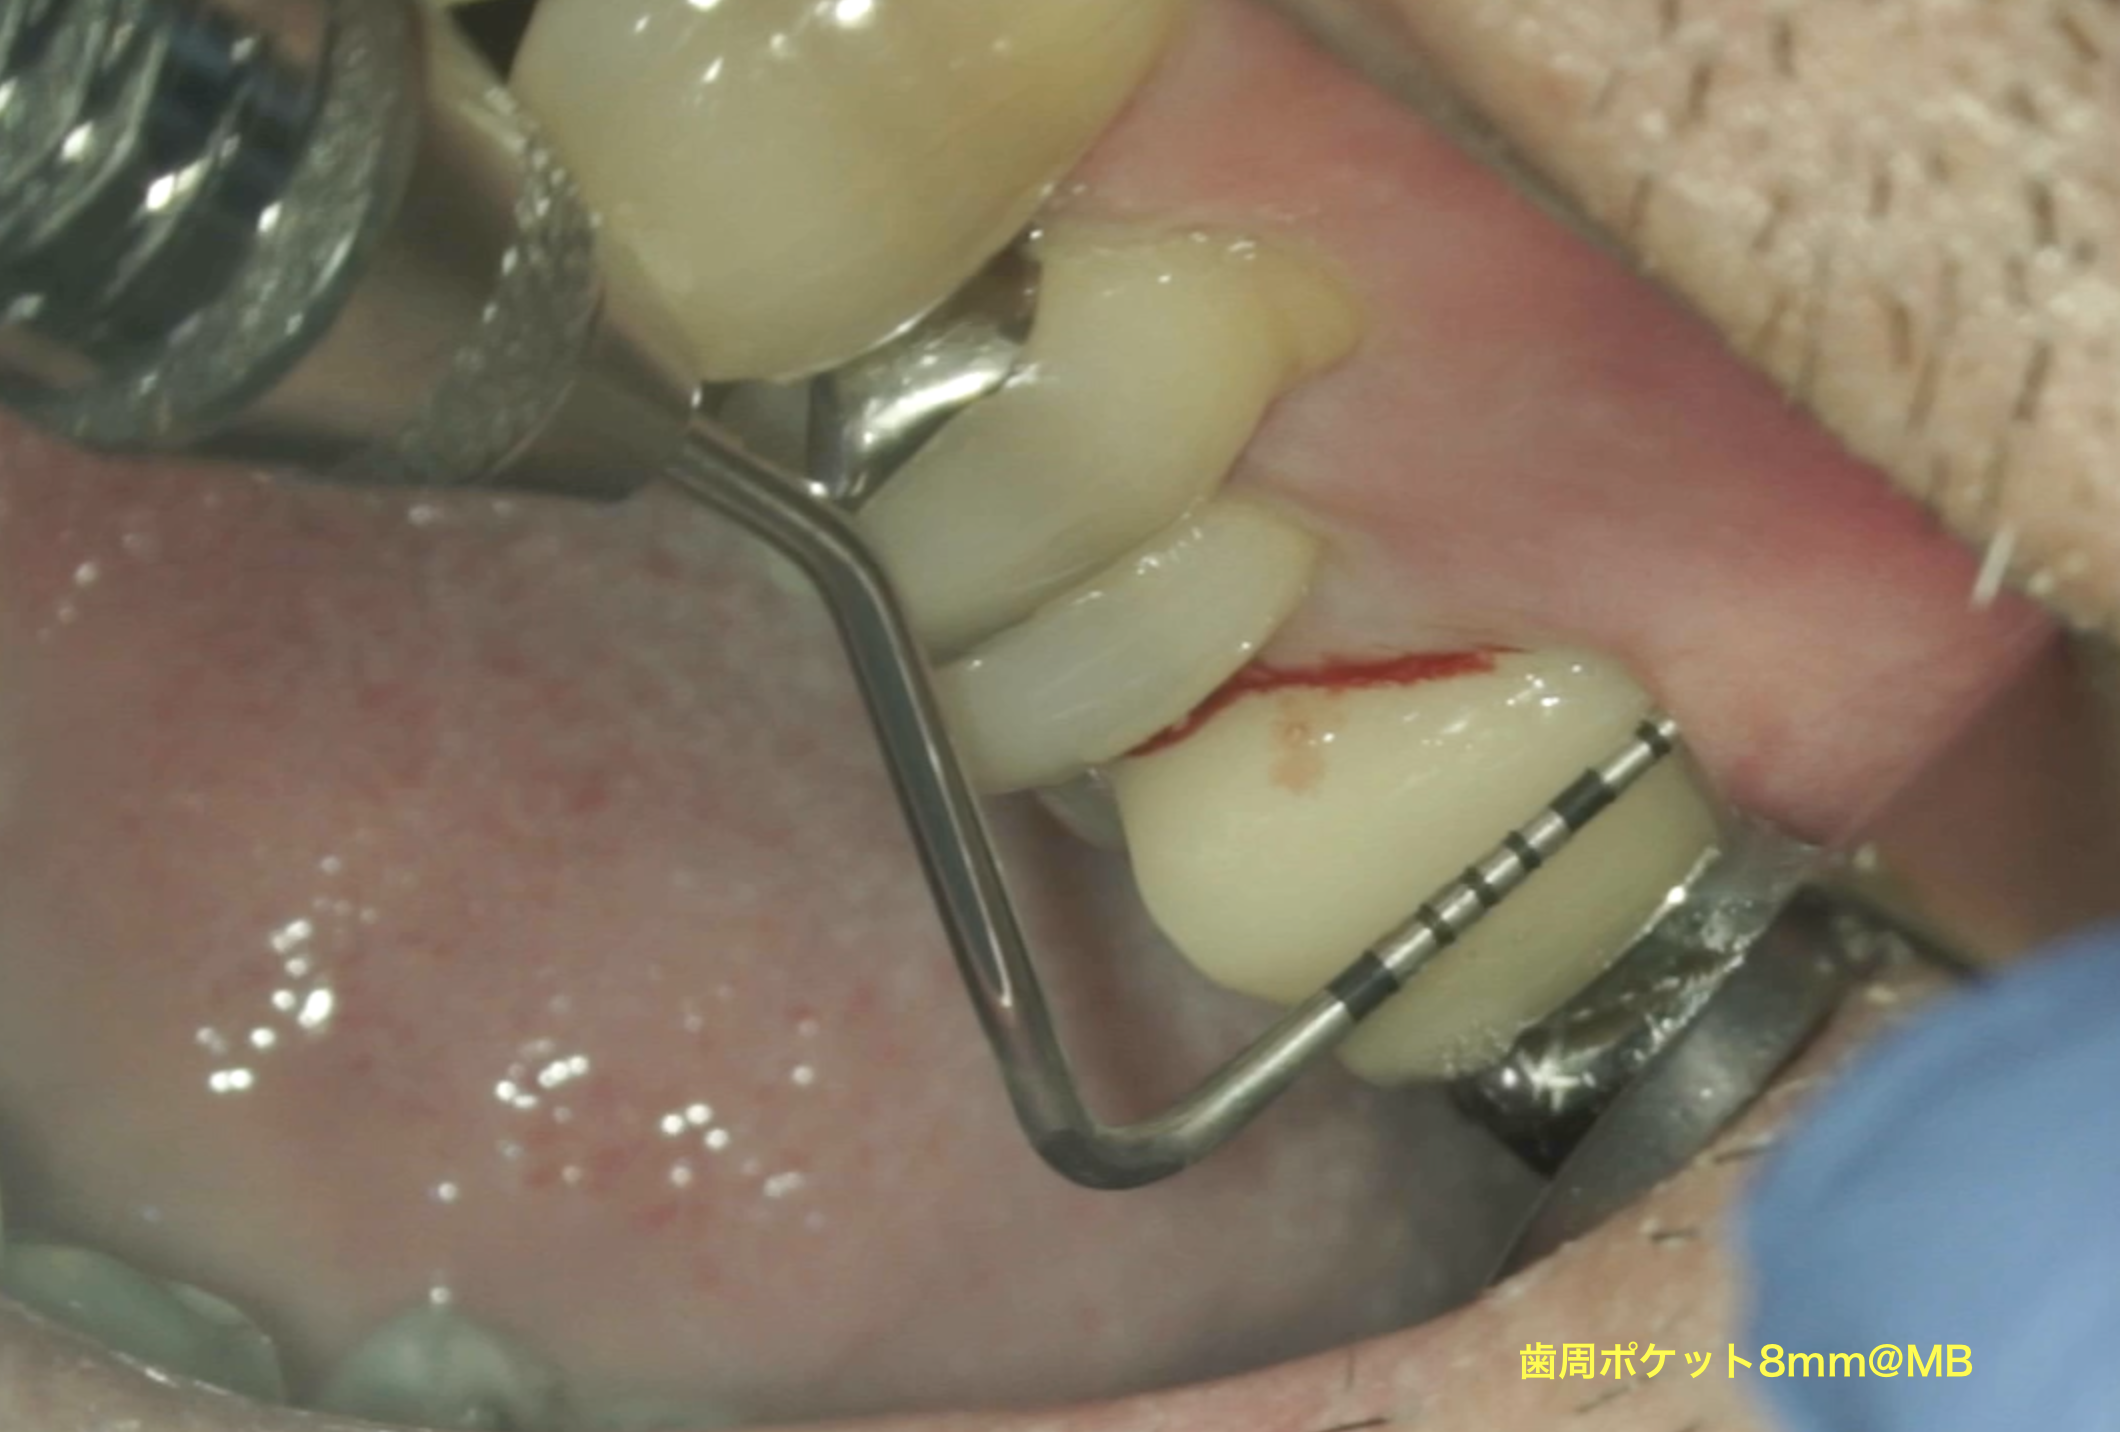

#14 の頬側には8mmの歯周ポケットがあった。

これが割れていると言われている所以の一つである。